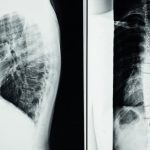

Les protrusions discales se produisent lorsque le disque intervertébral se déplace, exerçant une pression sur les nerfs environnants. Cette situation provoque des douleurs, des engourdissements ou même des faiblesses musculaires. Les tensions nerveuses résultantes peuvent devenir chroniques si elles ne sont pas traitées rapidement et efficacement.

La protrusion discale se produit lorsque le disque intervertébral entre deux vertèbres est déplacé de sa position normale, provoquant une compression des nerfs adjacents. Cela peut entraîner des douleurs aiguës, des engourdissements ou des faiblesses musculaires. Les patients ressentent fréquemment des douleurs chroniques qui affectent leur qualité de vie. La décompression neurovertébrale intervient pour atténuer les symptômes liés à cette condition.

Lorsqu’une protrusion discale se produit, le disque intervertébral se déplace et peut provoquer une compression des nerfs environnants. Cette situation peut entraîner des douleurs neuropathiques intenses, des sensations d’engourdissement et des faiblesses musculaires. La décompression neurovertébrale agit précisément en créant un espace entre les vertèbres grâce à une traction douce et contrôlée. En diminuant la pression sur les disques intervertébraux, elle permet de libérer les nerfs compressés, favorisant ainsi un rétablissement optimal des tissus environnants.